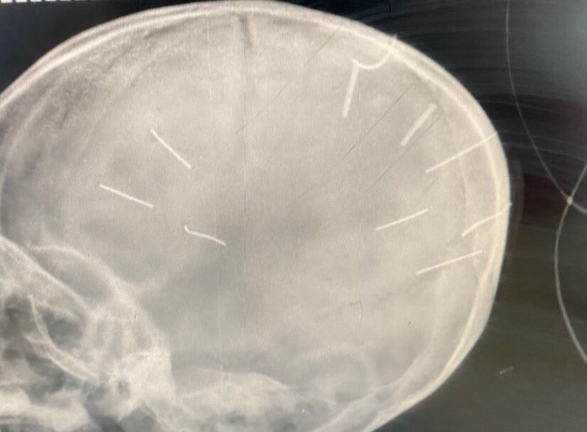

Kết quả phim chụp X-quang cho thấy, bé Đ.N.A., 3 tuổi, ở Canh Nậu, Thạch Thất, Hà Nội có đinh trong sọ, tiên lượng tử vong cao.

Hình ảnh phim chụp cho thấy hộp sọ của bệnh nhi có 9 đinh. (Ảnh: BVCC)

Đáng chú ý, tại Bệnh viện Đa khoa Xanh Pôn, kết quả phim chụp cắt lớp cho thấy bệnh nhi Đ.N.A. có hình ảnh như bị đinh bắn vào sọ. “Có 9 chiếc đinh. Bệnh nhân đang trong tình trạng rất nặng, đe doạ tử vong cao”, BS Kiên cho biết thêm.